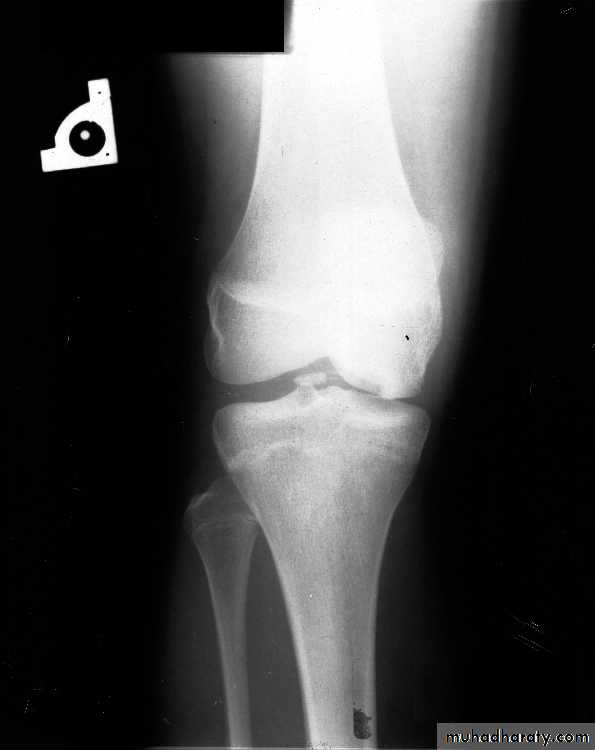

Frequent clinical assessment needed to look for progression & indication for surgery.Take x-ray for the knee & tibia to see the state of the epiphysis & state of the deformity.

X-ray:

• All previously mentioned cardinal features are seen with special features like;

• Features mostly seen in the medial compartment.

• There is varus alignment between tibia & femur.

• Picture better seen in the standing films.